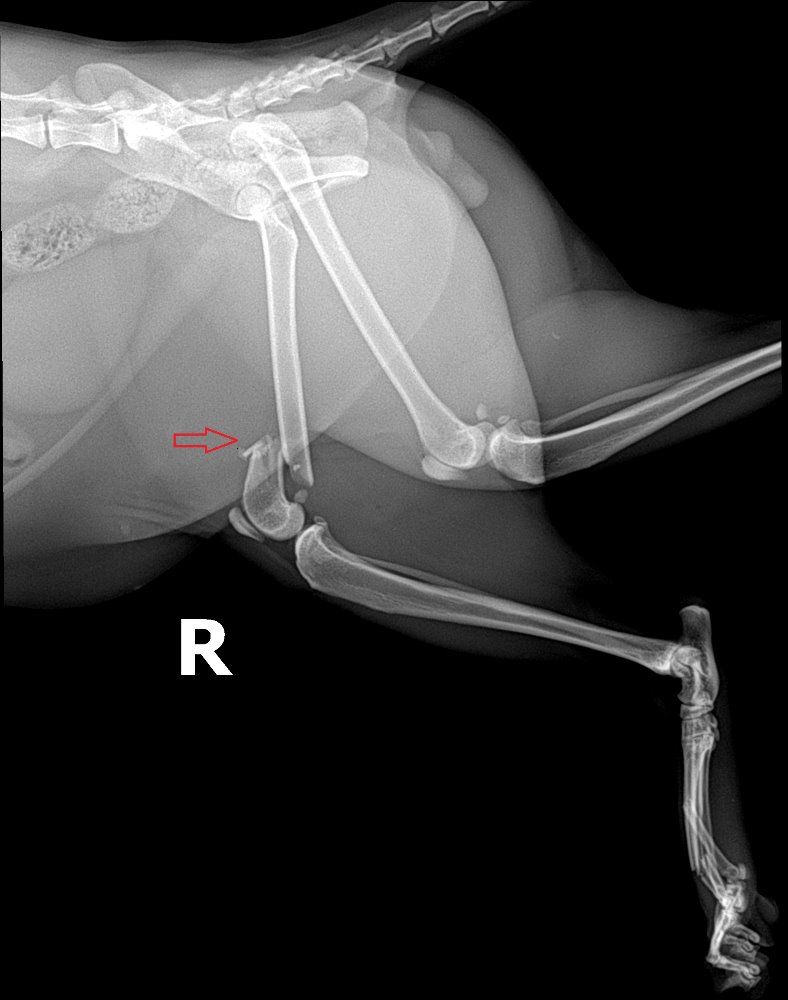

▪️Kočka, která spadla z výšky a přežila, mívá polámané končetiny a většinou přeraženou čelist, případně i obě. Operace jsou náročné a připraví majitele o slušnou částku peněz.

❗️FOTKY JSOU POUZE ILUSTRAČNÍ❗️